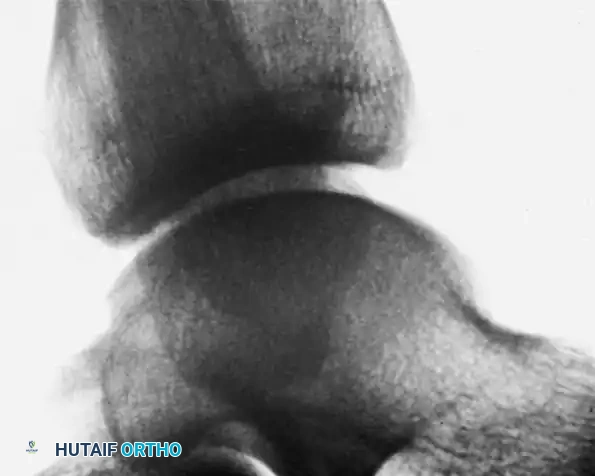

Morphological Characteristics

- Lateral Lesions: Typically traumatic in origin. They characteristically appear shallow, horizontal, and wafer-shaped. They are frequently elevated or completely detached, acting as loose bodies within the lateral gutter.

- Medial Lesions: Often insidious or microtraumatic in origin. They are characteristically deeper and cup-shaped. Although they may appear detached on imaging, they most frequently sit securely within their crater and are less likely to displace.